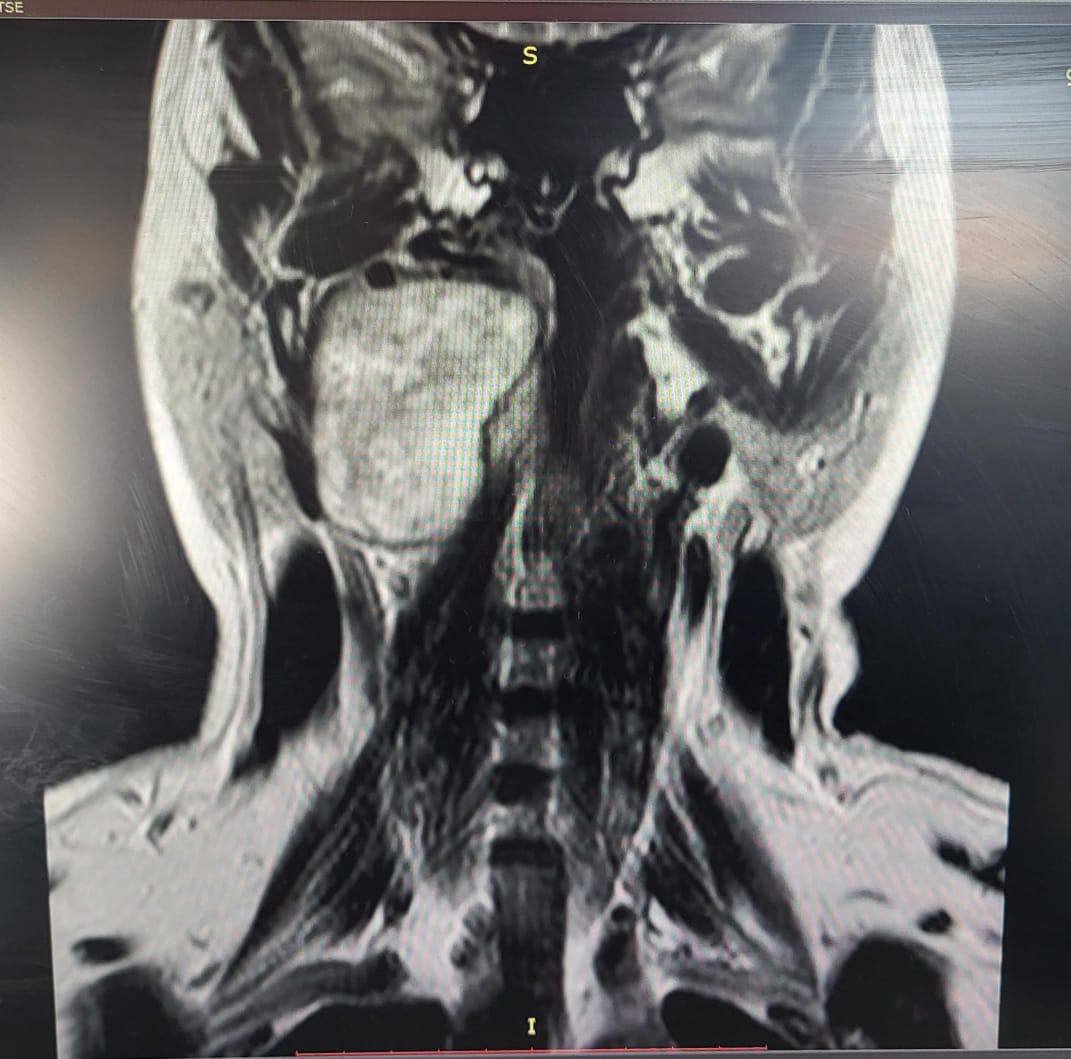

Сложную опухоль сумели прооперировать врачи ККБ №1 в Хабаровске

Женщина жаловалась на заложенность уха и увеличение небной миндалины. Результаты исследований выявили у нее в голове объемное образование. Это оказалась шваннома – доброкачественная опухоль, которая развивается из оболочек нервных клеток.

Отоларингологи и сосудистые хирурги приняли решение провести совместную операцию. В итоге все прошло успешно. Пациентка была выписана в удовлетворительном состоянии, никакого дискомфорта она теперь не испытывает.